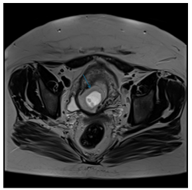

Figure 2: MRI, axial T2 TSE image.

Description: showing the gestational sac in the lower part of the uterus.

On the MRI the uterus is 107 x 60 x 64 mm.

At the level of the previous operation, ventrally, the myometrial muscle is missing for 18 mm. Within the proliferating endometrium, approximately a 27-mm egg sac with a 13-mm signal-poor, irregularly shaped area is depicted. The cervix is intact. A cyst of 24 mm and a smaller cyst of 16 mm can be seen in the left ovary. The walls of the smaller cysts are unevenly thick, but bleeding is not shown in them.

There is no free abdominal fluid.

The bladder is not full, its wall is intact.

Opinion: Cesarean scar pregnancy. There is a complex cyst in the left ovary.